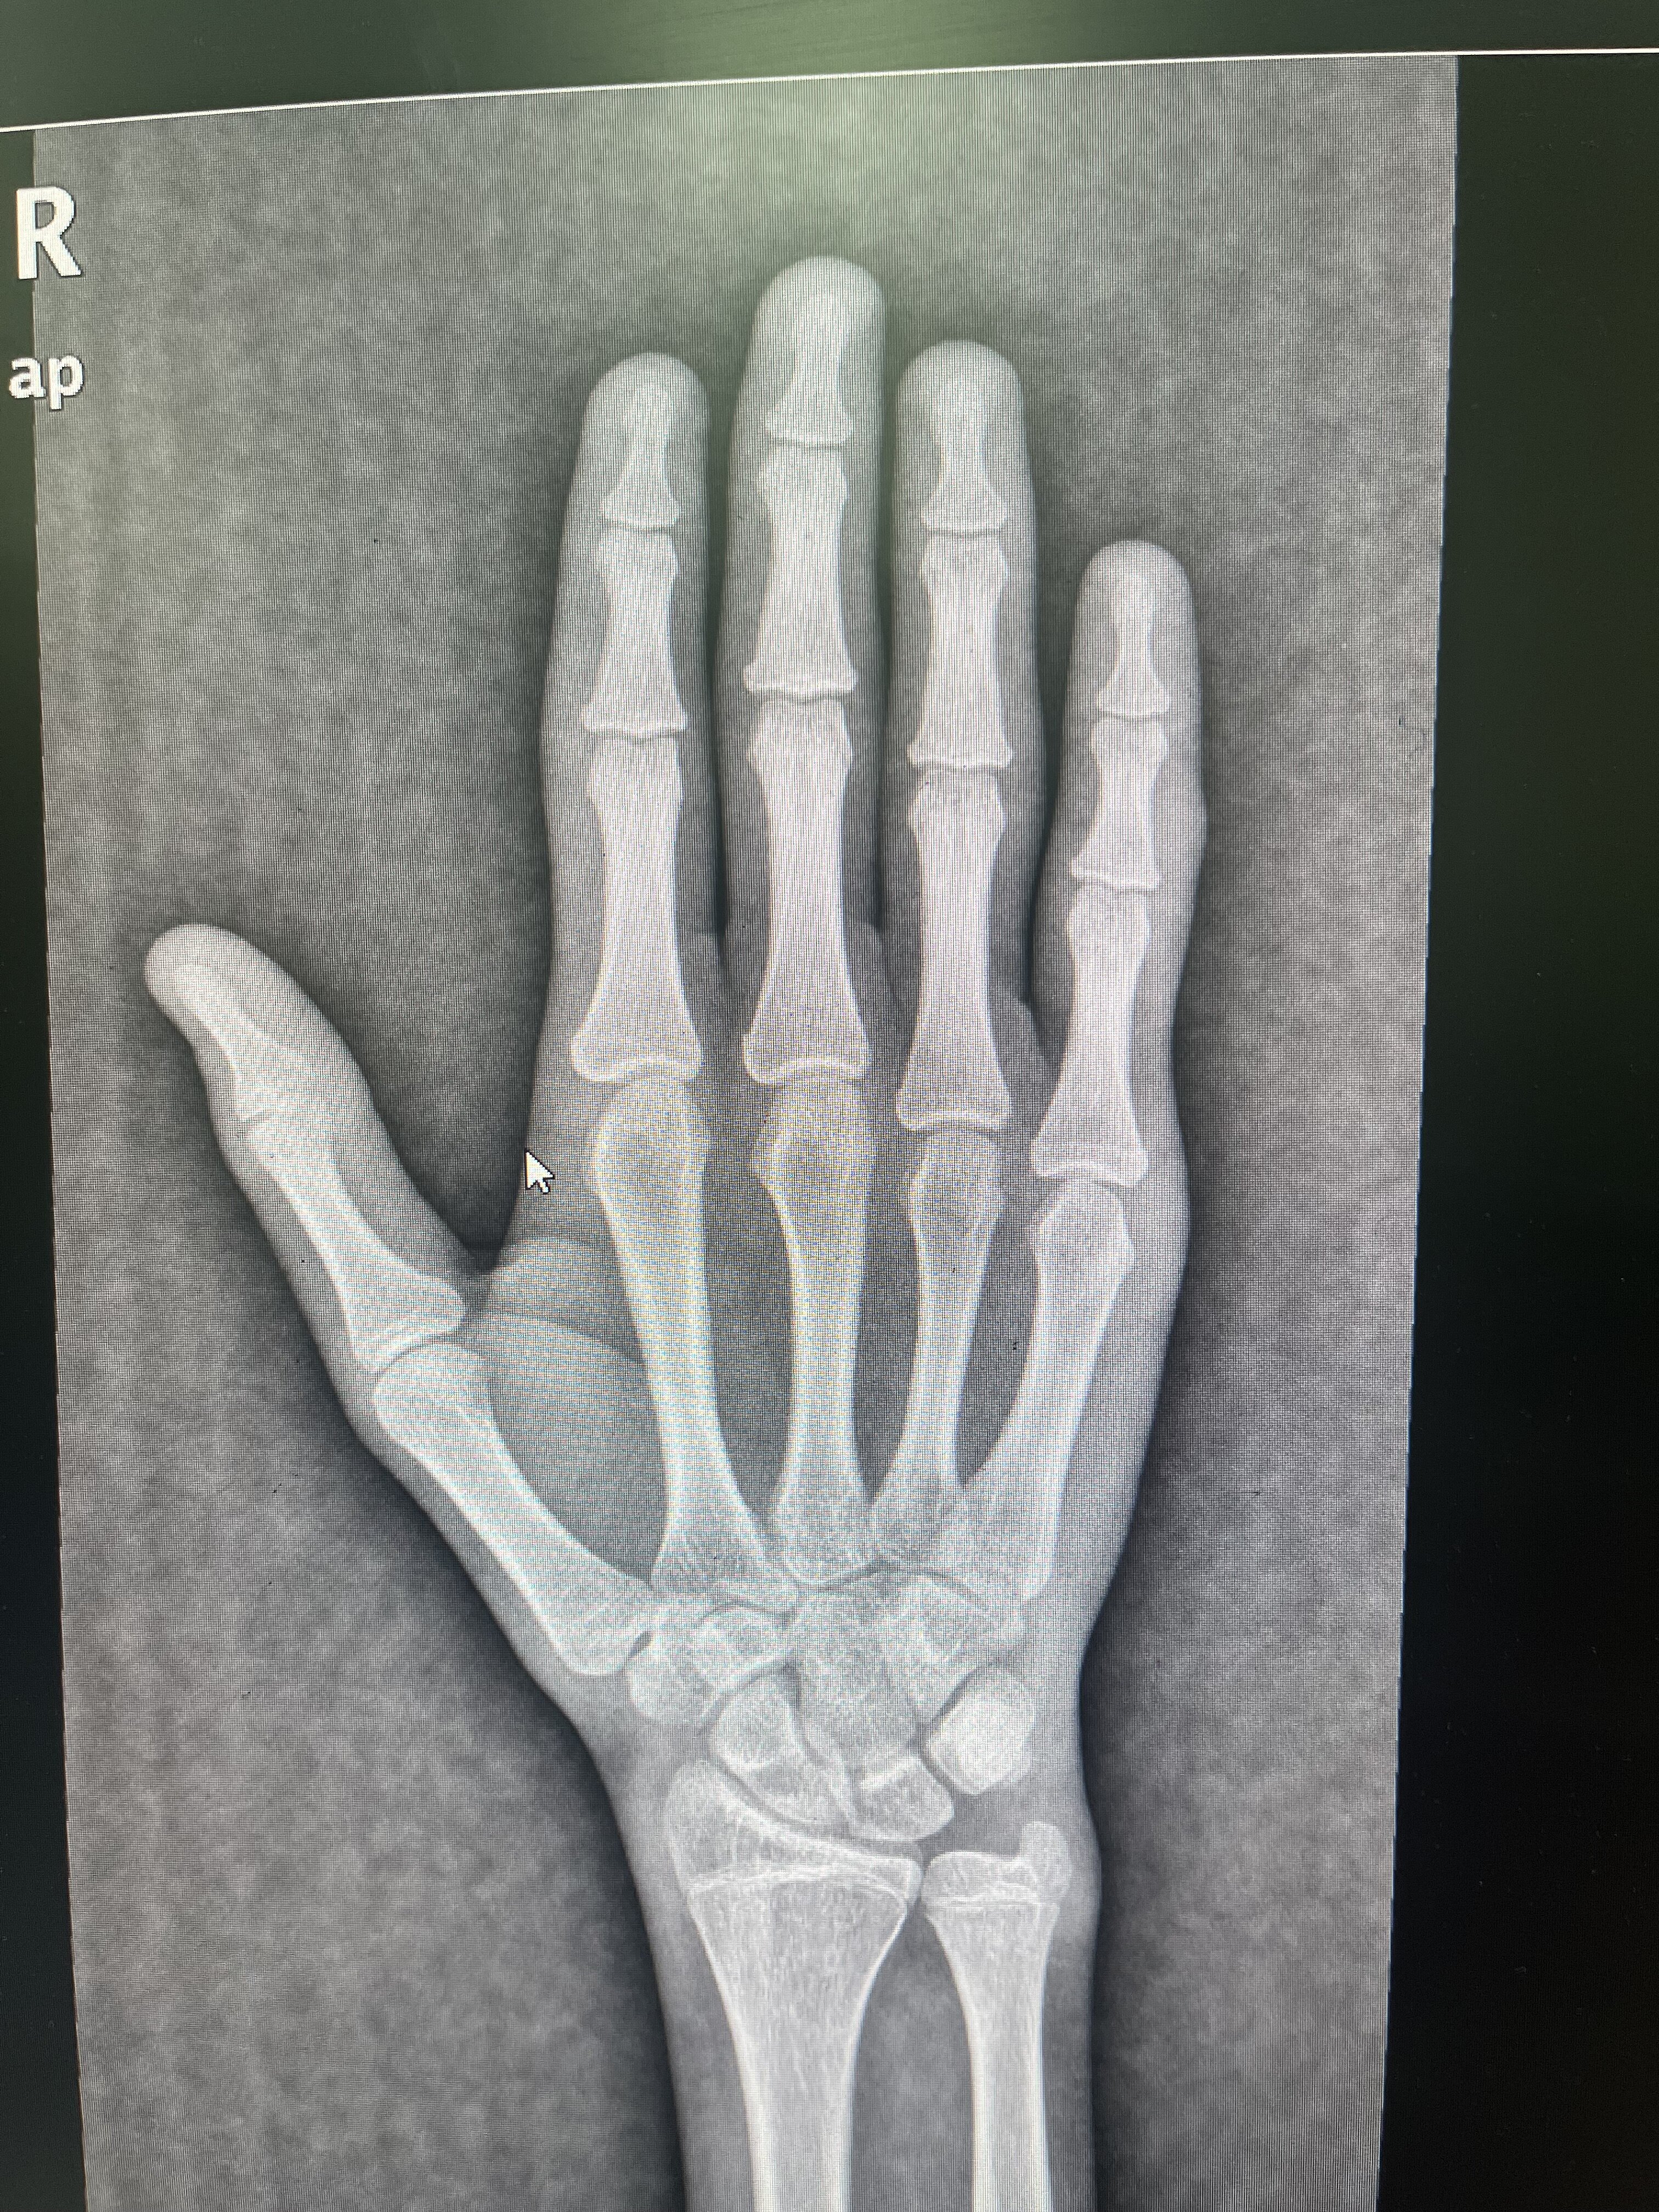

Is my growth plates still open

ngl looks close to fusion if youre 16 they look a bit advanced but theres like some data set to refer to to have it most accurate forgot what its called though 2-4cm ig you can check knee as well

pretty much closed, a lot of people are saying you might be able to grow a little but I doubt it, the plates are pretty much closed

they’re not closed completely I still have from 18-12 months of good hapits sleep and hormones to grow from 1-3 cm and it makes since

maybe a little bit but good chance u don’t grow anymore